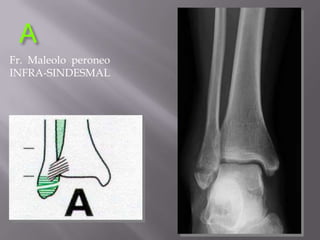

ClasificaciónBrunner y Weber (AO) 1982 segúnnivel de fractura de peronerespecto  a sindesmosisA : distal sindesmosisB  : al mismonivel de sindesmosisC  : proximal a sindesmosisMásaltamásdaño e inestabilidadClave Integridadligtibioperoneo posterior o susinserciones.

Fractura maleolar - 44BAA  Infra-sindesmalBTrans-sindesmalC  Supra-sindesmal

AFr.  Maleoloperoneo  INFRA-SINDESMAL